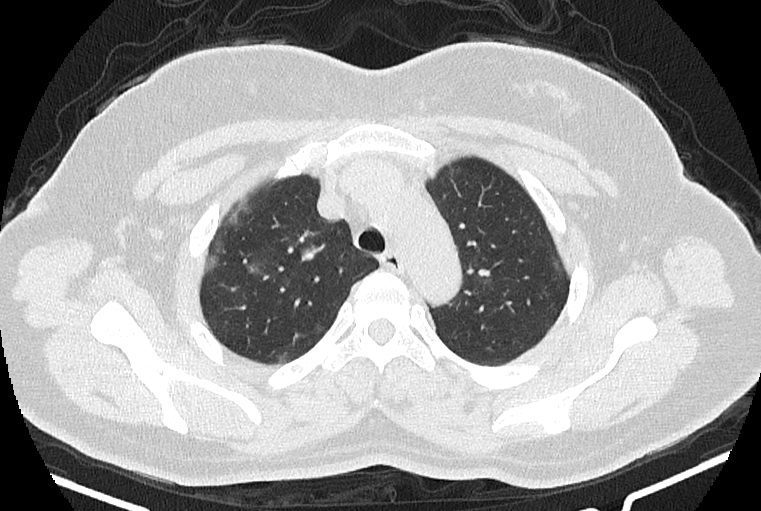

در HRCT از ريه ها(اسپيرال ، مولتي ديتکتور 16، مقاطع اگزيال با ضخامت 1mm بدون فاصله ) ، بدون كنتراست تزريقي :

-Ground glass opacities Patchy پراکنده در ريه ها مشهود است که مطرح کننده Viral pneumonia مي باشد . ( با درگيري 20 درصد حجم ريه )

نتیجه : Highly suggestive of COVID-19